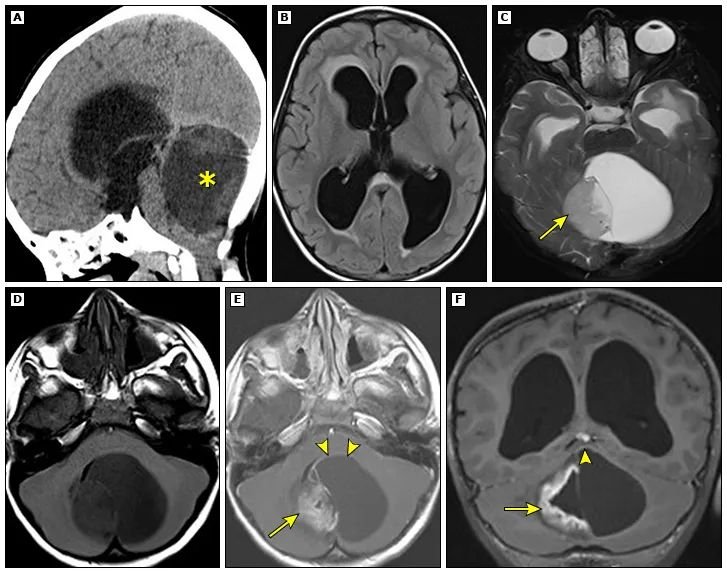

一名 5 岁儿童患有毛细胞星形细胞瘤,因梗阻性脑积水就诊。矢状位平扫 CT (A) 显示大的低密度小脑肿块 (*),该肿块压迫脑干并导致第三脑室和侧脑室扩大。横轴 FLAIR (B) MRI 显示经室管膜水肿,提示急性脑积水。横轴 T2- (C)、T1- (D) 以及横轴 (E) 和冠状 (F) 平面中的对比后 T1 加权图像显示带有壁结节的囊性小脑肿块(箭头)。壁结节内以及囊肿壁的一部分(箭头)内存在增强。